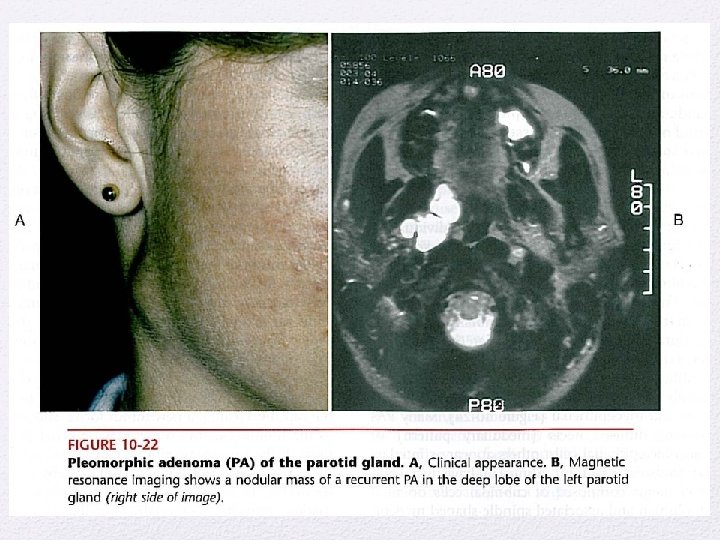

Benign salivary gland tumors • Pleomorphic adenoma • Monomorphic adenoma • Papillary cystadenoma lymphomatosusm • Oncocytoma